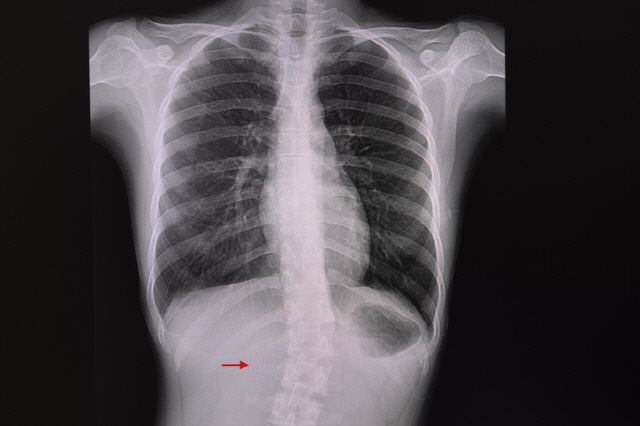

일반적으로 휜 척추가 직접 폐를 압박하는 경우는 없다. 다만, 정확히 말하면 만곡이 심해질수록 호흡 운동에 영향을 줘 폐 기능이 떨어질 수는 있다. 서울부민병원 척추변형센터 김용정 진료원장은 “몸의 한가운데에 있어야 할 척추가 옆으로 빠져 뒤틀리면, 호흡 운동에 중요한 역할을 하는 갈비뼈의 양쪽 대칭도 맞지 않게 된다”며 “그럼 갈비뼈 운동이 원활하게 일어나지 않아 폐 기능이 약간 감소할 수 있다”고 말했다. 그는 이어 “수많은 환자를 대상으로 연구한 결과, 휜 각도가 50~70도 정도일 때는 심각한 폐 기능 제한은 없고, 80도 이상일 때 나타나는 경우가 많다”고 말했다. 특히 100도가 넘어갈 정도로 심해지면 측만증뿐만 아니라 후만증까지 같이 오게 되는데, 이땐 폐의 용적이 줄어들어 폐 기능이 더 많이 감소할 가능성이 있다.